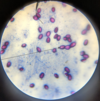

Leishmania sp.: Promastigotes

- Leishmania sp.*: Promastigotes

- Extracellular forms*

Leishmania sp.: Amastigotes

Divided & intracellular - Only in macrophages